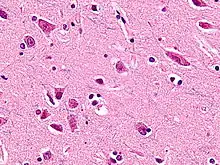

Веретенообразные нейроны или нейроны фон Экономо (названы в честь их первооткрывателя Константина фон Экономо[1]), описанные в 1929 году, являются особым классом нейронов. Для них характерно большое веретенообразной формы тело, постепенно сужающееся в единичный апикальный аксон на одном конце и единственный дендрит на противоположном конце. Кроме того, что у других типов нейронов чаще встречается большое количество дендритов, полярная форма веретенообразных нейронов уникальна. Они найдены только в двух очень ограниченных районах головного мозга гоминид: в передней поясной коре (ППК) и во фронтоинсулярной коре. Недавно эти нейроны были найдены и в дорсолатеральной префронтальной коре мозга человека[2]. Веретенообразные клетки также есть в мозге горбатых китов, финвалов, косаток, кашалотов[3][4] , афалин, серых дельфинов, белух,[5], африканских и индийских слонов.[6]

Веретенообразные нейроны — очень большие клетки относительно других клеток мозга, и они позволяют осуществлять быстрый процесс передачи информации по сравнительно крупному мозгу человекообразных, хоботных и китообразных. Некоторые ученые считают, что они играют важную роль в различных возможностях и нарушениях, связанных с приобретением знаний, в основном уникальных для людей — от восприимчивости к синдрому саванта и идеального слуха до дислексии и аутизма.

В 1999 году невролог профессор Джон Аллман (John Allman) с коллегами из Калифорнийского технологического института первым опубликовал отчет о веретенообразных нейронах, специфичных только для ППК гоминид. У людей и шимпанзе было найдено больше веретенообразных нейронов, чем у орангутанов и относительно более крупных горилл.

Аллману с коллегами[8] пришлось изучать мозг на клеточном уровне, чтобы исследовать, как веретенообразные нейроны функционируют на структурном уровне, концентрируя внимание на их роли как «диспетчеров» эмоций. Команда Аллмана выяснила, что веретенообразные нейроны помогают передавать нейронные сигналы из глубоких внутренних частей коры к относительно далеким частям мозга.

Больше всего веретенообразных нейронов передней поясной коры найдено в организме человека, меньше у некрупных человекообразных обезьян и еще меньше у крупных. У людей и бонобо они часто обнаруживаются в скоплениях по 3-6 штук. Анализ V слоя ППК гоминид показал, что среднее количество этих нейронов у орангутанов в ППК — примерно 9 на срез; они редкие, составляют 0,6 % от всех клеток среза. У горилл их примерно 22, то есть они встречаются чаще, составляют 2,3 %; у шимпанзе их примерно 37, они обильны, составляют 3,8 %; у карликовых шимпанзе — примерно 68, они обильны и собраны в скопления, составляют 4,8 %; у людей — примерно 89, они также обильны и собраны в скопления, составляют 5,6 %.[10]

У всех изученных приматов веретенообразных нейронов фронтоинсулярной коры было больше в правом полушарии, чем в левом. Несмотря на то что у шимпанзе и бонобо было найдено больше веретенообразных нейронов в ППК, число этих нейронов во фронтоинсулярной коре было много больше у горилл (данные по орангутанам еще не получены). У взрослого человека 82 855 таких клеток, у гориллы — 16 710, у карликового шимпанзе — не более чем 1 808, несмотря на то, что шимпанзе и карликовые шимпанзе гораздо ближе к человеку.